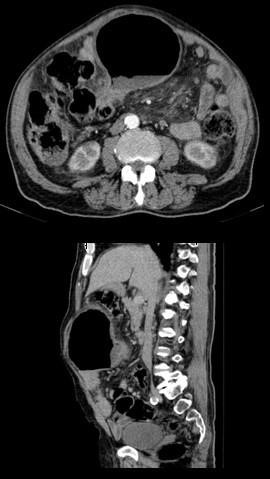

The blood tests revealed leucocytosis and elevated C-reactive protein. An abdominal computed tomography showed an 11 cm air-filled central structure, apparently originating from the small bowel, described as a closed loop small bowel obstruction (Fig.1).

Figure 1: CT scan showed an 11 cm air-filled central structure